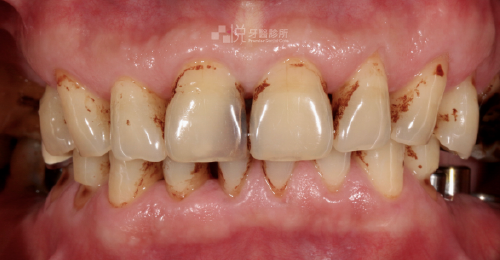

全口重建並非單純的「缺哪顆補哪顆」,當口腔內出現多處缺牙、磨損嚴重、甚至影響到發音、飲食困難或是不敢自信的開口大笑時,就屬於全口重建的治療範疇。